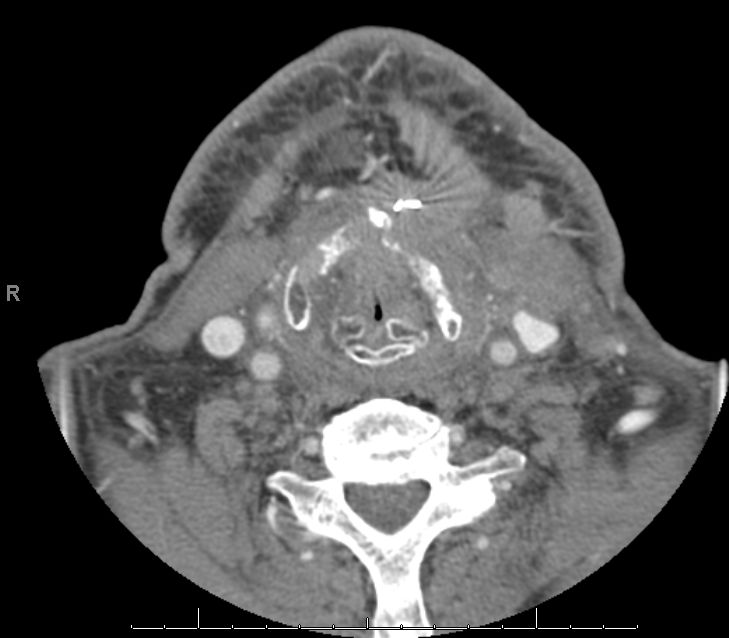

Fortgeschrittenes Larynx - Ca mit Zerstörung des Kehlkopfskeletts.![]() |